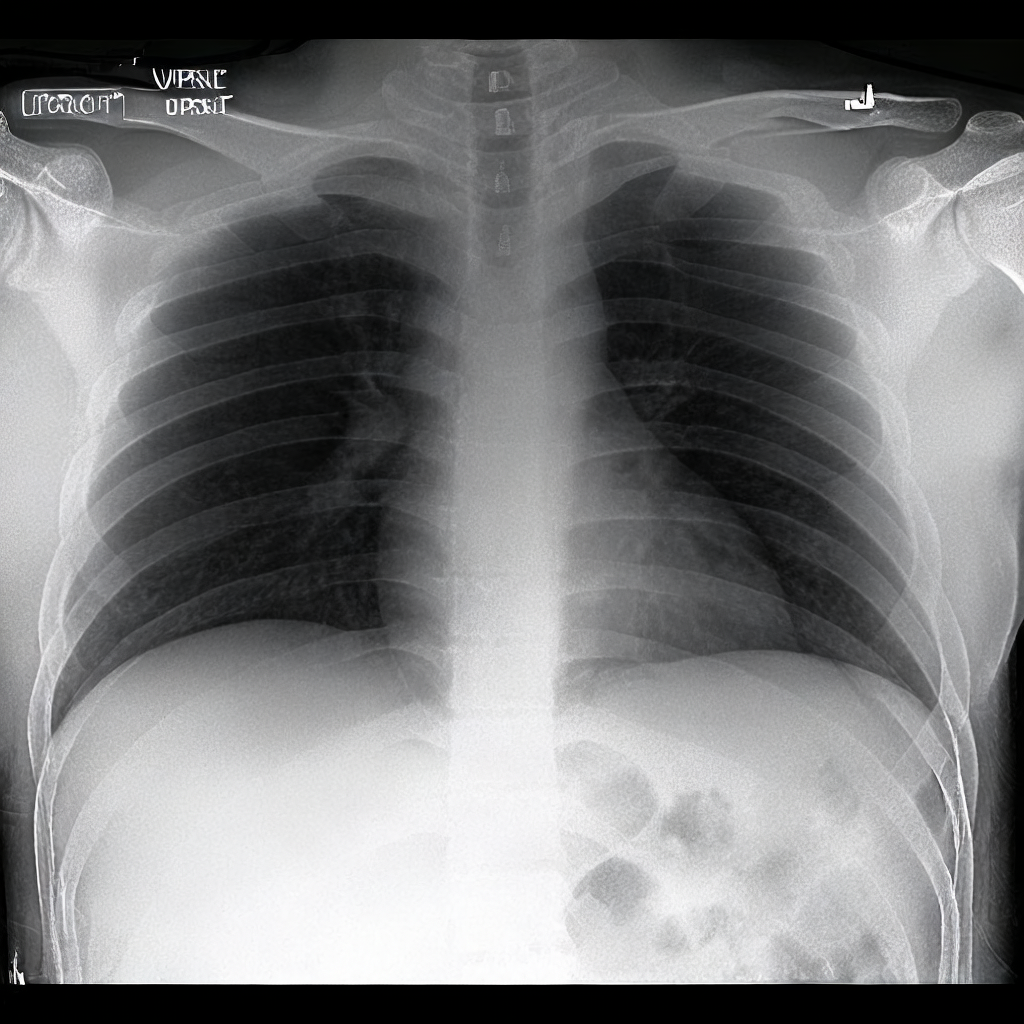

Diffusion models have recently gained significant traction due to their ability to generate high-fidelity and diverse images and videos conditioned on text prompts. In medicine, this application promises to address the critical challenge of data scarcity, a consequence of barriers in data sharing, stringent patient privacy regulations, and disparities in patient population and demographics. By generating realistic and varying medical 2D and 3D images, these models offer a rich, privacy-respecting resource for algorithmic training and research. To this end, we introduce MediSyn, a pair of instruction-tuned text-guided latent diffusion models with the ability to generate high-fidelity and diverse medical 2D and 3D images across specialties and modalities. Through established metrics, we show significant improvement in broad medical image and video synthesis guided by text prompts.

In this work, we focus on the ability of LDMs to generate novel datasets to overcome class imbalances traditionally associated with medical data, and potentially reduce the need for manual annotation of medical 2D and 3D data. We present MediSyn, a pair of text-guided latent diffusion models for broad medical 2D and 3D modality synthesis. To overcome the scarcity of labelled medical data, we leverage a vast corpus of more than 5 million image-caption pairs and 100,000 video-caption pairs collected from the public domain across numerous medical specialties, and integrate comprehensive natural language annotations to develop a pair of versatile diffusion models for the medical domain.

Our work, akin to Sagers et al. and Chambon et al. focuses on synthesizing multi-class medical datasets through text prompts. In their work, Chambon et al. adapt a pre-trained LDM, Stable Diffusion, on a corpus of chest x-rays (CXR) and their corresponding radiology reports to generate CXR displaying different disease states [29]. Similarly, Sagers et al. use DALL-E to synthesize skin lesions across all Fitzpatrick skin types [30].

Our findings demonstrate Medisyn’s remarkable ability to generate high-fidelity and diverse medical images, image sequences and volumetric scans across various medical subspecialties and imaging modalities. Other medical text-driven diffusion models, such as TauPETGen [42] for tau PET images and GenerateCT [43] for chest CT volumes, have proven successful in generating high-quality images that accurately depict anatomical features and clinical conditions. However, these models are constrained to a single imaging modality and anatomical region, thereby restricting their applicability. Moreover, they were trained on relatively small datasets sourced from a limited number of institutions, which could lead to more biased outputs. In contrast, Medisyn, having been trained on one of the largest publicly accessible medical image and video datasets to date, is equipped to synthesize data that cover numerous medical disciplines, population groups, and disease states. Leveraging our two models, we can synthesize new medical datasets as well as augment existing ones, potentially improving a wide array of medical machine learning tools, both general and specialized. Additionally, our models can minimize the need to repeatedly fine-tune on specific datasets for generating different imaging modalities, thus reducing computational costs for academic labs.